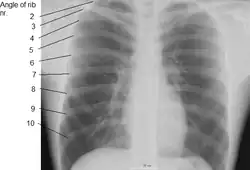

The angle of a rib (costal angle) may both refer to the bending part of it, and a prominent line in this area, a little in front of the tubercle. This line is directed downward and laterally; this gives attachment to a tendon of the iliocostalis muscle. At this point, the rib is bent in two directions, and at the same time twisted on its long axis.

The distance between the angle and the tubercle is progressively greater from the second to the tenth ribs. The area between the angle and the tubercle is rounded, rough, and irregular, and serves for the attachment of the longissimus dorsi muscle.